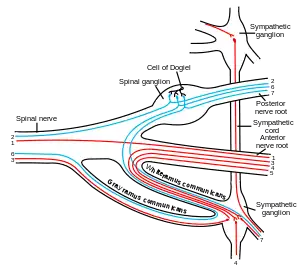

A spinal nerve with its ventral and dorsal roots. The dorsal root ganglion is the "spinal ganglion", following the dorsal root. | |

The dorsal root ganglia lie in the intervertebral foramina. The anterior and posterior spinal nerve roots join just beyond (lateral) to the location of the dorsal root ganglion.

Medulla spinalis The formation of the spinal nerve from the posterior and anterior roots

The formation of the spinal nerve from the posterior and anterior roots Scheme showing structure of a typical spinal nerve.